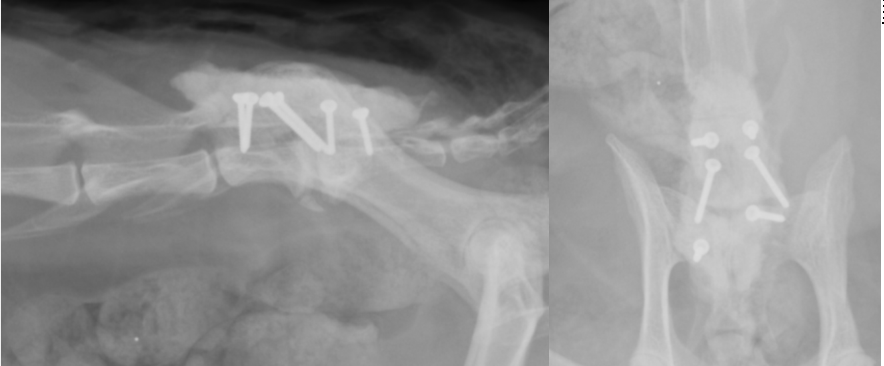

圧迫が解除されたらスクリューをうち、セメントによって固定します。

スクリューとセメントで固定されています。

斜めに入っているスクリュー2本が経関節固定のスクリューで、他の4本は骨セメント固定用のスクリューです。

真ん中の2つが経関節固定のスクリューで、前後2本ずつ入っているのが骨セメント用スクリューです。

それを覆う四角形のものが骨セメントです。